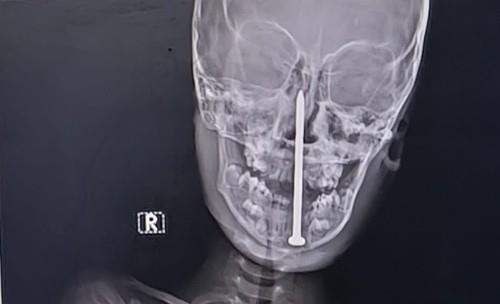

U indijskoj saveznoj državi Utar Pradeš sedmogodišnji dečak iz okruga Balrampur doživeo je strašnu nezgodu dok se igrao. Naime, dečak je pao je na ekser dužine 8 centimetara, koji mu je probio glavu.

U galeriji pogledajte rendgenske snimke eksera koji se zabio dečaku u glavu:

Tamo su lekari uradili MR i CT snimke, koji su pokazali da je osam centimetara dug ekser prošao opasno blizu velikog krvnog suda u mozgu.